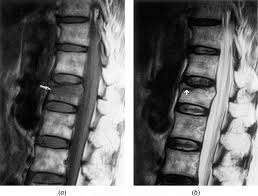

Acute And Chronic Vertebral Compression Fractures Clinical Mri

Acute And Chronic Vertebral Compression Fractures Clinical Mri from clinical-mri.com